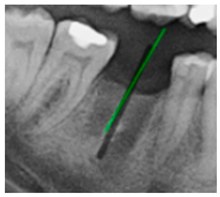

3.3. Comparison with Clinical Ground Truth and AI-Assisted Framework

This subsection presents a comparison between the dentist-defined clinical gold standard and the predictions generated by our AI-assisted framework to evaluate the reliability of implant pathway orientation. The result is shown in Table 10, the preserved DPR validation set was used for verification, and the AI-assisted framework results were overlaid onto the original DPR images to provide a clear visualization. The AI-assisted framework pathways (green lines) were highly consistent with the dentists’ ground-truth annotations (black lines). Quantitatively, the mean squared error (MSE) between the predicted implant direction and the dentists’ planned results was only 1.537° across multiple test images. This minimal deviation validates the proposed system’s technical feasibility. It highlights its clinical potential to provide accurate and stable guidance for implant placement, thereby reducing the risk of misalignment and supporting efficient preoperative orientation.

Comparison between model-predicted pathways and dentist-planned pathways.